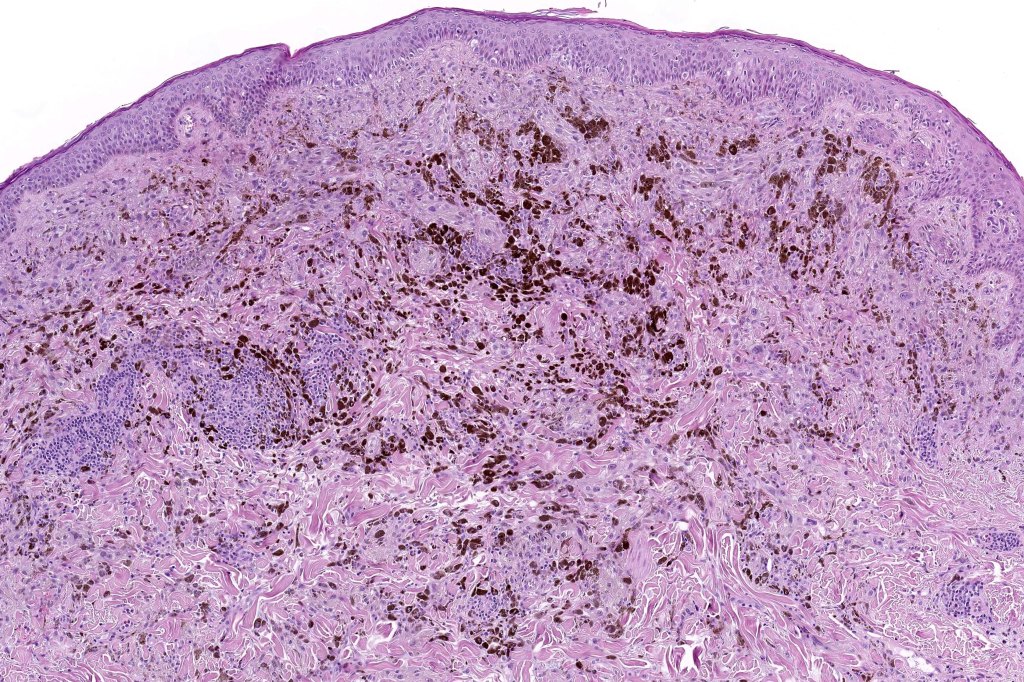

•Symmetrical, circumscribed wedge-shaped infiltrate-most common growth pattern with the broad base uppermost, deeper aspect extends along appendageal structures & neurovascular bundles with a fasciular or plexiform pattern

•Plexiform growth pattern very occasionally seen (plexiform spindle cell nevus (Barnhill)

•Melanophages